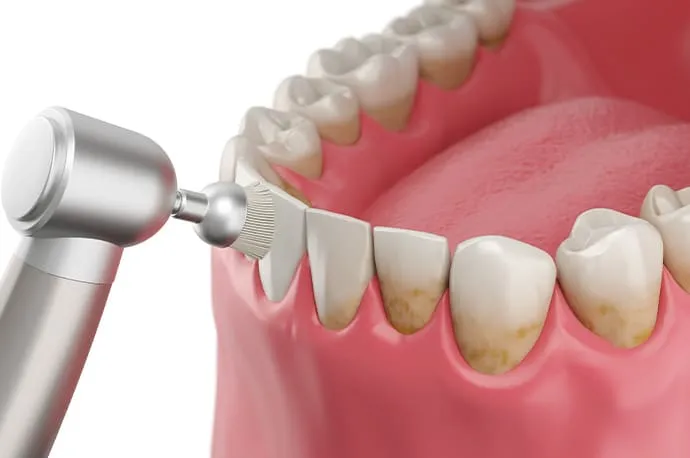

歯石の除去

歯の表面や歯ぐきの下の歯石を取り除き、炎症を防ぎます。

PMTC(プロフェッショナルケア)

回転ブラシなどを使い、歯の汚れや着色をしっかり落とします。